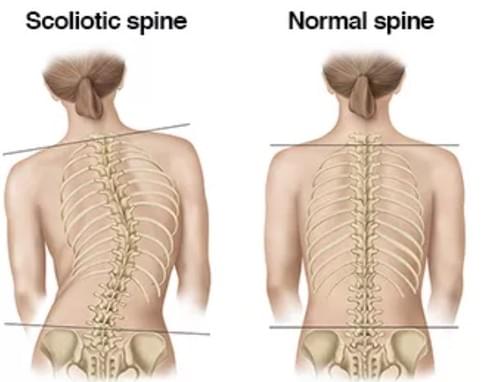

如有脊椎錯位或椎間盤突出, 就有機會壓迫神經線, 令一些症狀出現!

小童脊柱側彎

小童脊柱側彎最大機會出現的問題: -高低膊 -經常橋腳或盤膝坐 -坐直背脊會覺得容易攰 -走路很容易跌倒,容易受傷 -左右鞋底的磨損情況有所差異選擇日期與時間